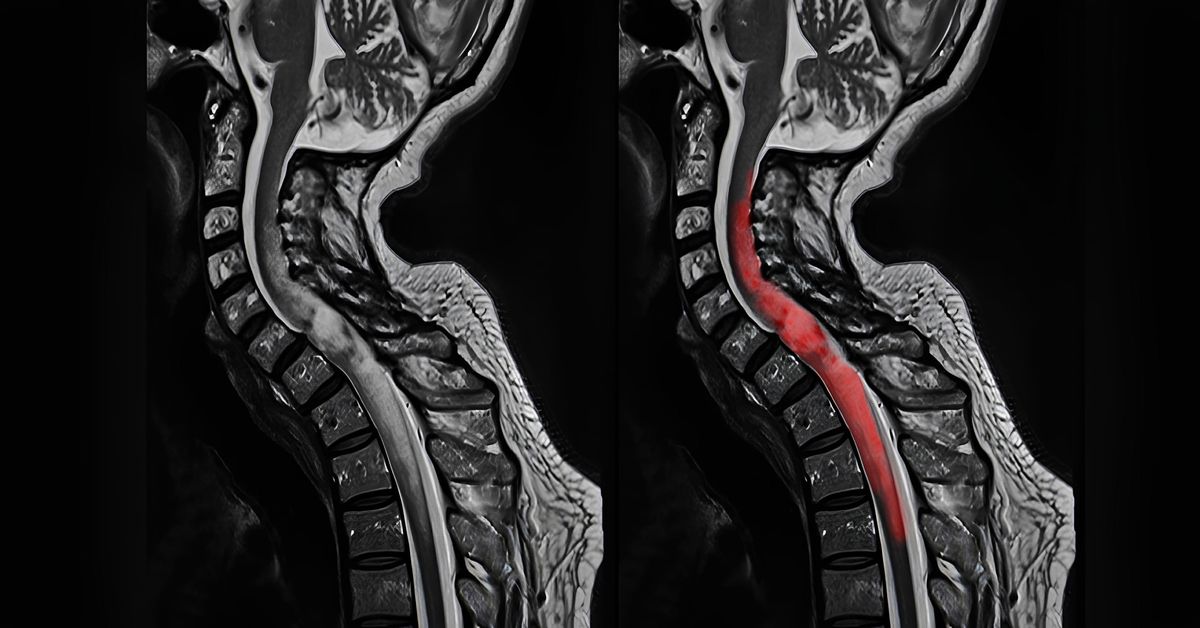

Omurga tümörleri, sinir sistemi ve hareket kabiliyeti üzerinde ciddi etkiler yaratabilir. Bu nedenle tedavi planı büyük bir titizlikle hazırlanır. Tanı aşamasında manyetik rezonans (MR) ve bilgisayarlı tomografi (BT) gibi ileri görüntüleme yöntemleri kullanılır. Bu sayede tümörün yeri, boyutu ve omurilikle ilişkisi detaylı biçimde değerlendirilir. Bu aşamadan sonra omurga tümörü tedavisi, tümörün türüne, büyüklüğüne ve hastanın genel sağlık durumuna göre şekillenir.

Omurga tümörleri, kemikleri, omurilik zarları ve omuriliğin kendisinde gelişebilir. Bu oluşumlar farklı bölgelerde ortaya çıkabilir. Bu tümörler farklı yapılardan kaynaklanabilir. Bu tümörler iyi ya da kötü huylu olabilir ve sinir dokularına baskı yaparak ciddi nörolojik sorunlara yol açabilir. Bu nedenle omurga tümörü tedavisi, yalnızca tanı konulmuş hastalar için değildir. Belirli risk ve belirti gruplarına sahip bireyler için de değerlendirilmesi gereken önemli bir süreçtir.

Omurga tümörleri, omurga kemiklerinde veya omuriliğe yakın dokularda gelişen iyi ya da kötü huylu oluşumlardır. Bu durum, zamanla sinir dokularına baskı yaparak ağrı, uyuşma veya güçsüzlük gibi şikâyetlere yol açabilir. Uzun süredir geçmeyen bel, sırt veya boyun ağrısı yaşayan bireylerde bu tür tümörlerin olasılığı mutlaka değerlendirilmelidir.

Bu noktada Omurga Tümörü Tedavisi, hem tümörün yayılımını kontrol altına almak için uygulanır. Ayrıca omurga ve sinir sistemine zarar vermeden fonksiyonel bütünlüğü korumayı amaçlar. Tedavi, omurilik basısı veya nörolojik kayıp gibi durumlarda uygulanır. İdrar ya da dışkı kontrolünde değişiklik görüldüğünde ise aciliyet taşır. Cerrahi müdahaleler, radyoterapi ve kemoterapi gibi yöntemler tümörün türüne ve konumuna göre belirlenir. Bu yöntemler tek başına ya da kombine biçimde kullanılabilir.